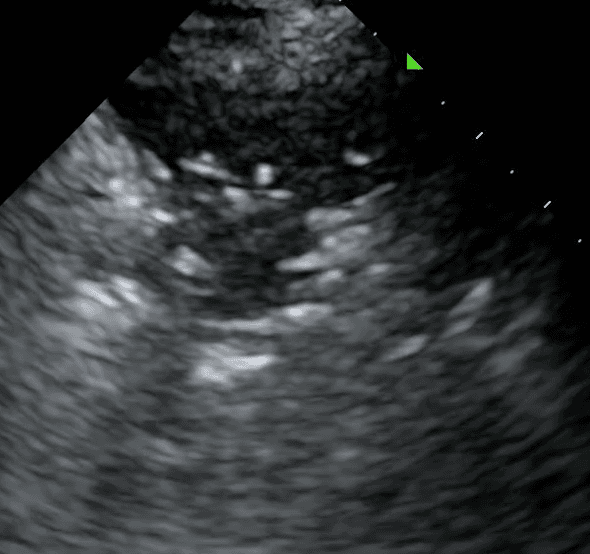

Consolidated lung appears dark due to its increased density and in some instances, may take on a similar texture to the liver. This is often referred to as “hepatization of the lung.”

Air bronchograms are air-filled bronchi that remain patent within the surrounding consolidated lung, They appear as hyperechoic structures within the hypoechoic consolidation. They may resemble multiple millimeter-long, lentil-shaped structures or branching tubular structures.

A shred sign represents the boundary between consolidated (abnormal) and aerated (normal) lung tissue. It appears as an irregular (shredded/fractal) line next to normal lung.